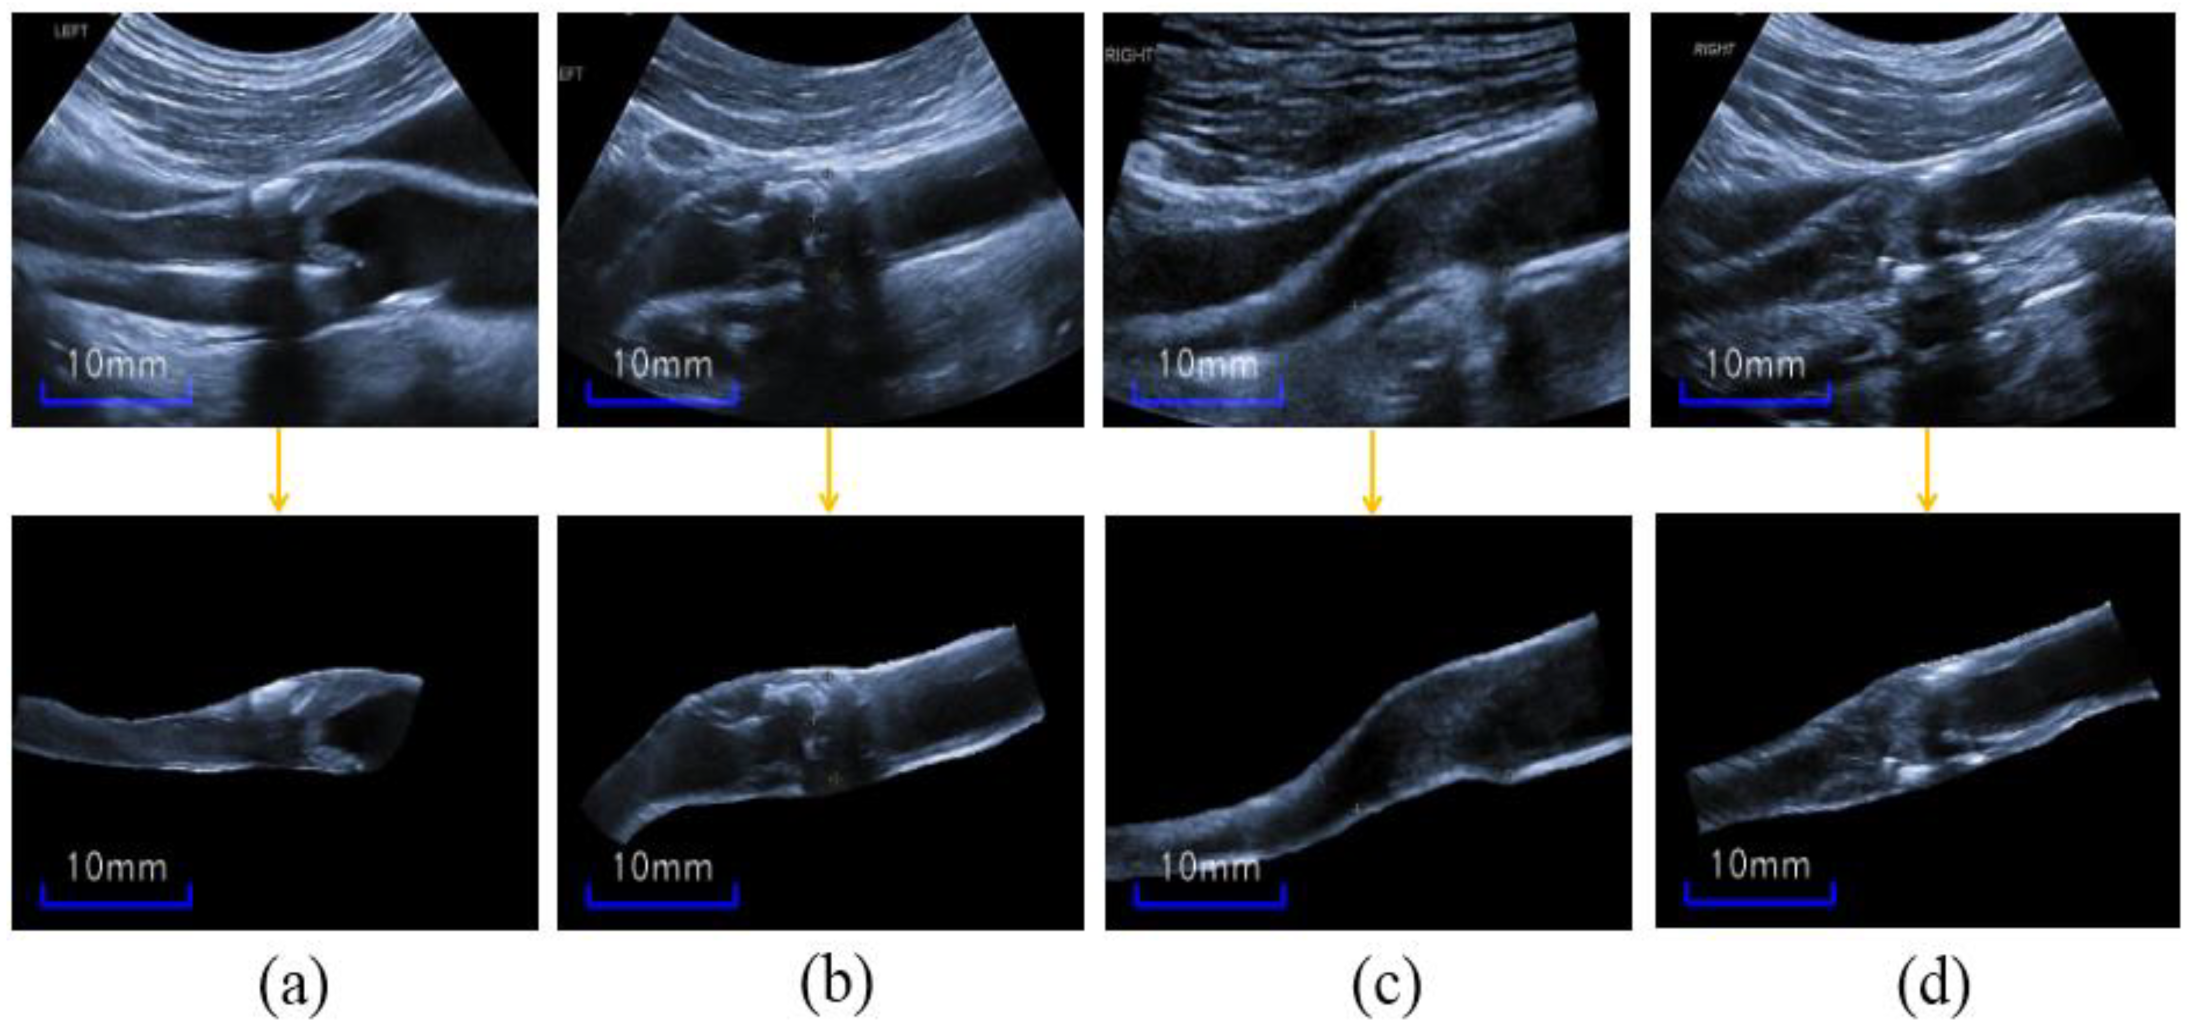

3.1.2. Cropped-Blood-Vessel Image Augmentation (CBVIA)